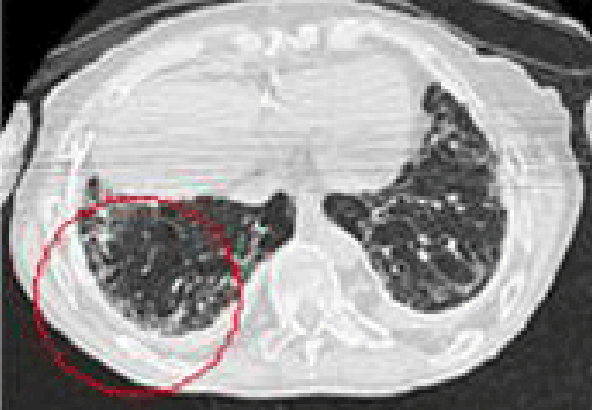

석면폐증(잠복기 약 15~40년)

잠복기가 약 15~40년에 걸친 석면으로 인한 석면폐증에 대한 CT사진

석면에 의한 폐 조직에 상처로 나타나는 폐섬유화 증상

• 폐의 섬유화로 희게 나타나며 공기집이 생겨 벌집모양으로 나타남

석면폐증의 병 유형(의심형, 초기형, 진행형) 및 폐기능 장해단계(정상, 경도장해, 고도장해)에 따라 1~3급으로 구분

• 석면폐증의 병 유형 : 폐섬유화 소견에 따라 의심형, 초기형, 진행형으로 구분